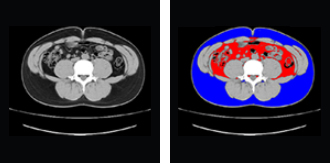

上の図はヘソ周りのCT画像です。

赤色が内臓脂肪、青色が皮下脂肪を示しています。

CTでヘソ周りを1スライス撮影して、内臓脂肪と皮下脂肪を計測する検査です。内臓脂肪面積(左記画像赤色の部分)が100cm2以上となると内臓脂肪型肥満と言われます。更に脂質異常、高血糖、高血圧の内、2つ以上が該当するとメタボリックシンドロームとなり生活習慣病を合併するリスクが高まります。